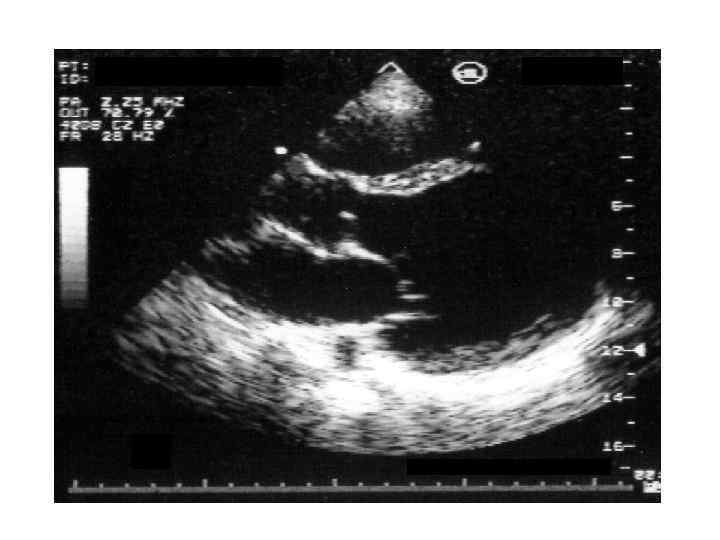

Рестриктивная кардиомиопатия Клиника и диагностика • Первичный амилоидоз • - Диагностика Моноклональная иммуноглобулинопатия – 90 % б-х Гипогаммаглобулинемия Плазмацитоз в костном мозге > 50% б-х Тромбоцитоз - 10% б-х На ЭКГ – «псевдоинфарктные изменения» , нарушения сердечного ритма и проводимости На ЭХОКГ – утолщение стенок левого и правого желудочка, утолщение эндокарда клапанов, регургитация, жидкость в перикарде, расширение предсердий, выраженное нарушение расслабления

Рестриктивная кардиомиопатия Клиника и диагностика • Первичный амилоидоз • - Диагностика Моноклональная иммуноглобулинопатия – 90 % б-х Гипогаммаглобулинемия Плазмацитоз в костном мозге > 50% б-х Тромбоцитоз - 10% б-х На ЭКГ – «псевдоинфарктные изменения» , нарушения сердечного ритма и проводимости На ЭХОКГ – утолщение стенок левого и правого желудочка, утолщение эндокарда клапанов, регургитация, жидкость в перикарде, расширение предсердий, выраженное нарушение расслабления